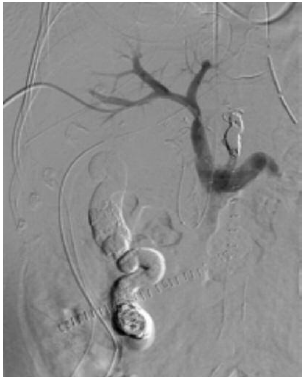

A 60-year-old male patient affected by alcoholic cirrhosis presented with a

history of hepatic encephalopathy, portal hypertension with previous variceal

bleeding, moderate ascites, and Barcelona Clinic Liver Cancer stage A

hepatocellular carcinoma (HCC). The patient had no other relevant comorbidities

in past medical history. A pretransplant contrast-enhanced computed tomography

(CT) revealed a cirrhotic liver associated with moderate ascites, splenomegaly,

and the presence of 2 different portosystemic shunts through the coronary vein

and through a 17.5-mm mesocaval shunt, associated with grade 2 portal vein

thrombosis, and a 22-mm HCC in S8 (Figure 1).

Figure 1. Pretransplant Contrast-Enhanced Computed Tomography Scan